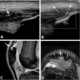

Rupture of quadriceps tendon

In human anatomy, the quadriceps tendon works with the quadriceps muscle to extend the leg. All four parts of the quadriceps muscle attach to the shin via the patella (knee cap), where the quadriceps tendon becomes the patellar ligament. [Source: Wikipedia ]